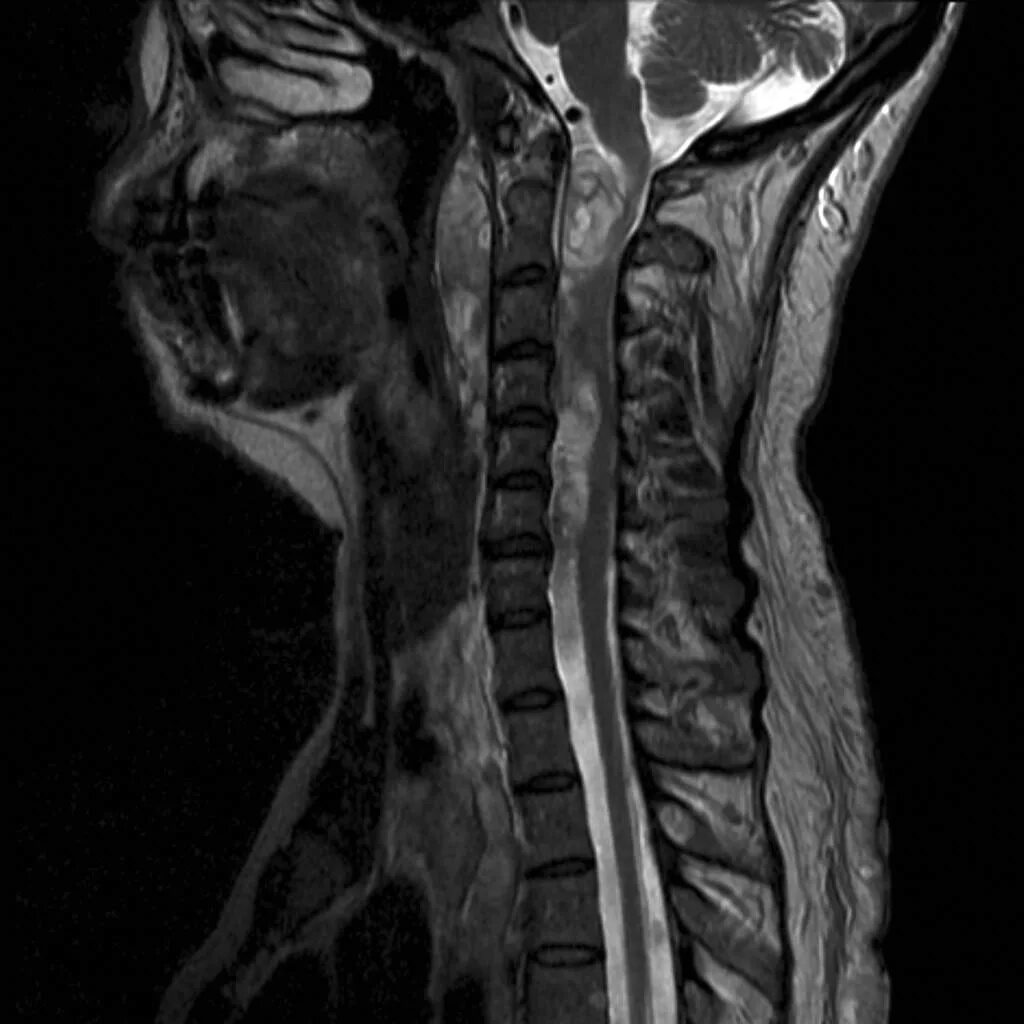

Spine mri